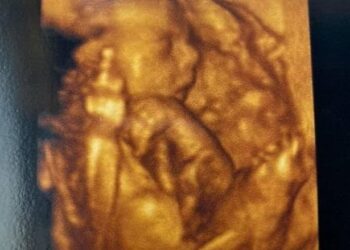

Read moreOs ingleses Chelsea Furnival e seu marido Adrian Witt foram surpreendidos quando acompanhavam o exame de ultrassom 4D, realizado ainda...